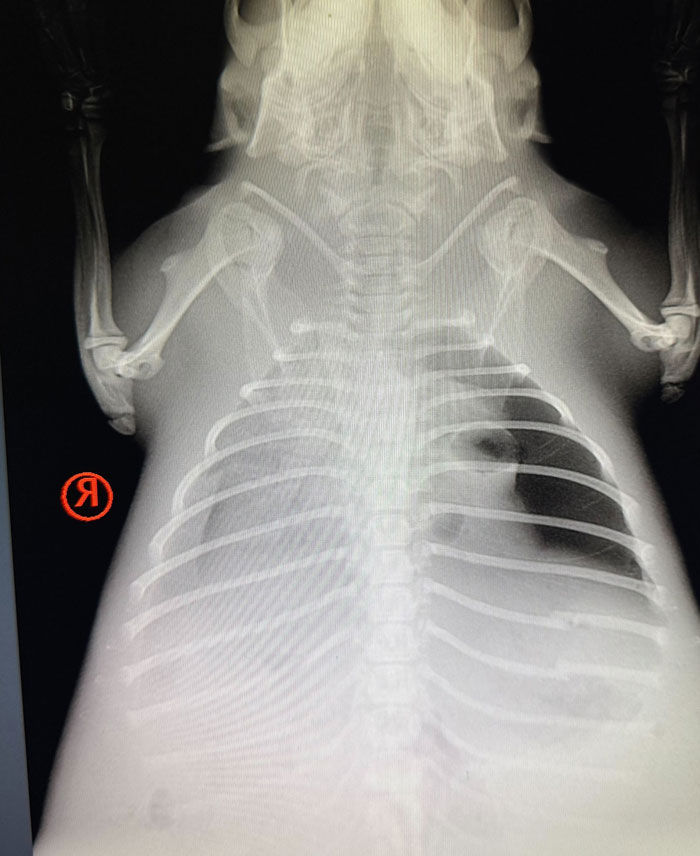

Once she arrived, the team gave the sick animal a meticulous medical exam and discovered that she was likely suffering from pneumonia and internal injuries. “On admission, our veterinary team noted that she was weak with labored breathing,” BRWC wrote on Facebook. “[X-rays] indicate pneumonia or fluid from near-drowning as well as trauma on the left side.”